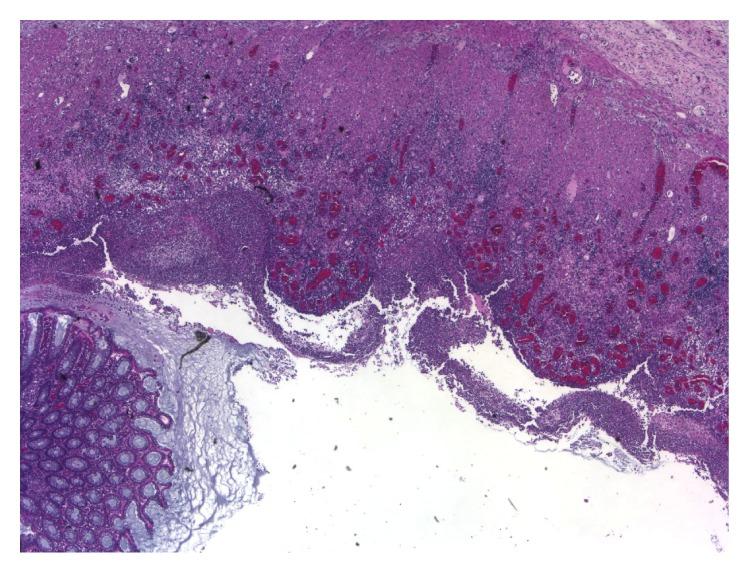

8

Morphology of rectal mucosa of patients with shigellosis.

Rev Infect Dis. 1991 Mar-Apr;13 Suppl 4:S314-8. doi: 10.1093/clinids/13.supplement_4.s314.